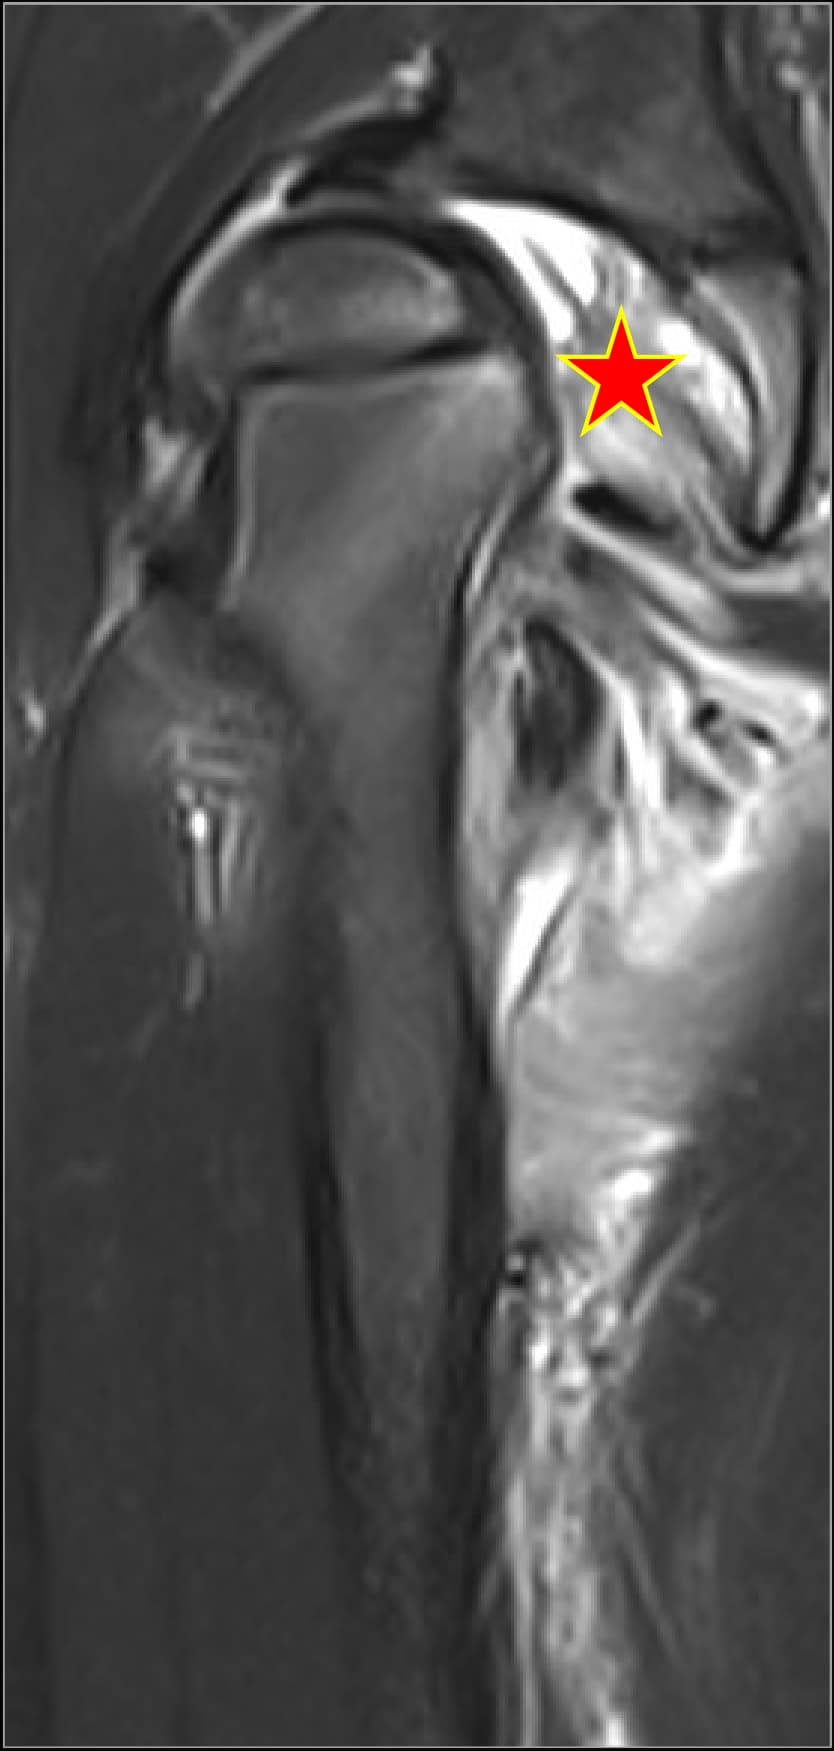

Septic arthritis cases